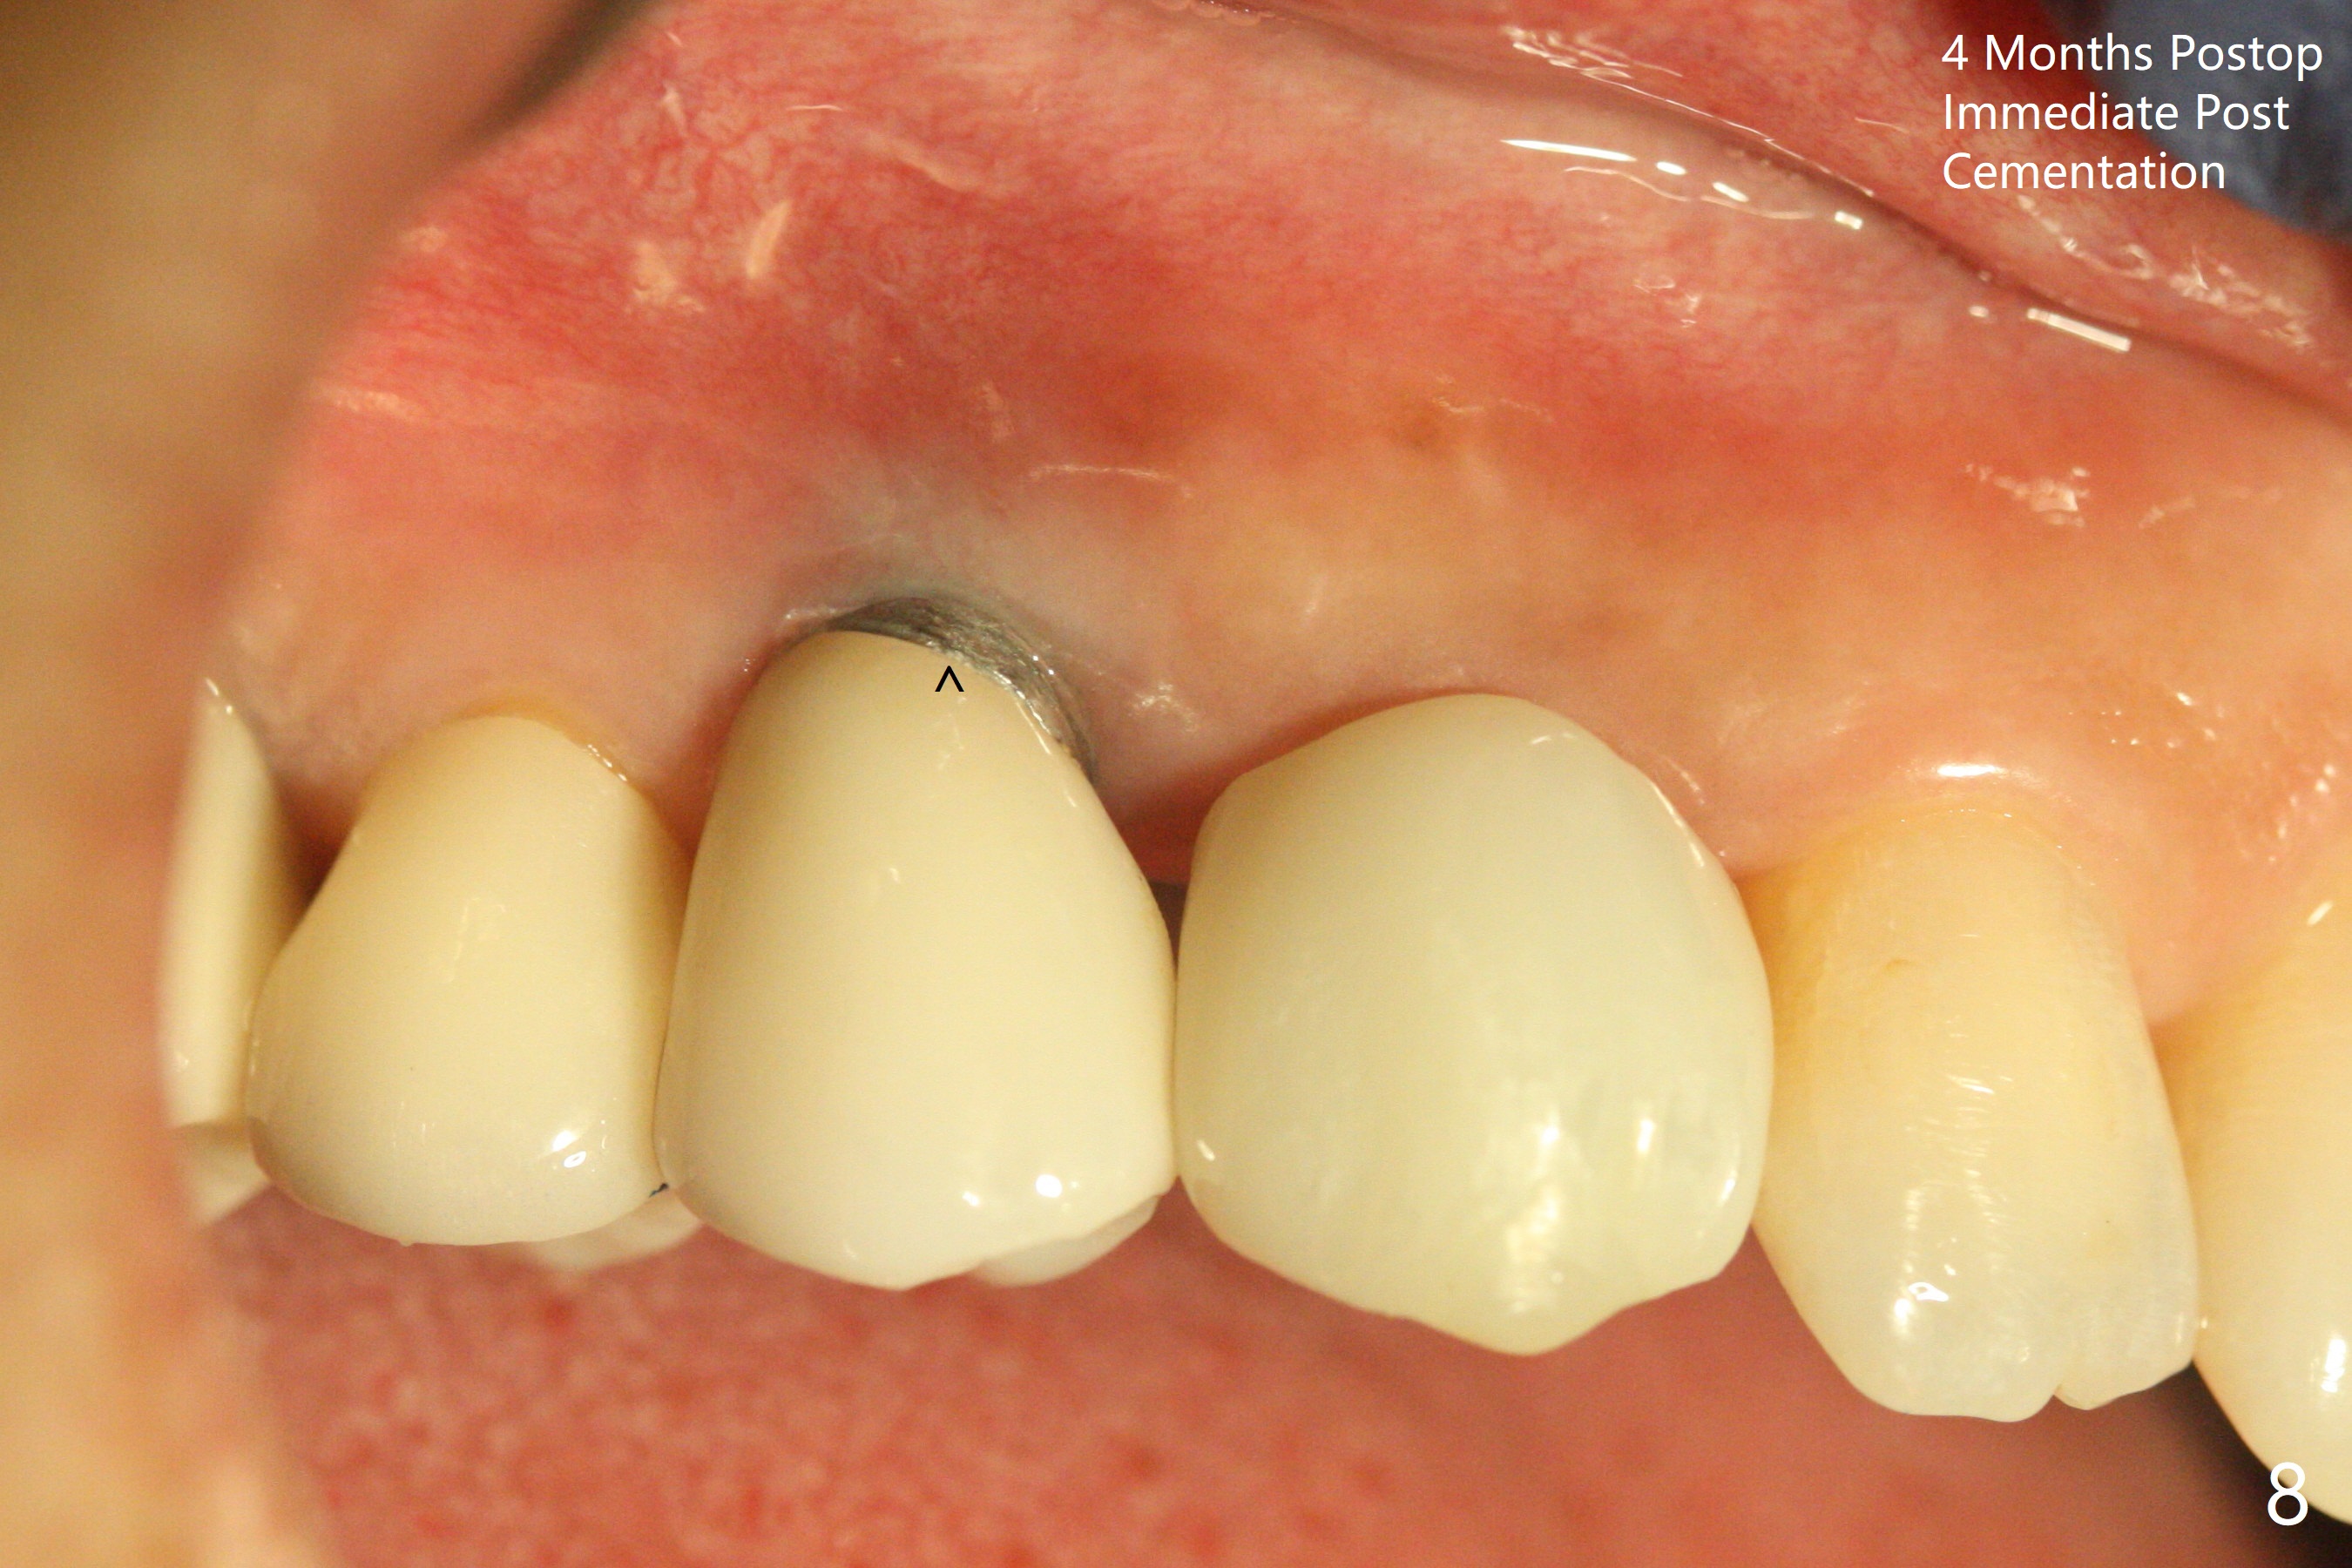

When the recemented crown at #6 is removed, the post is found to have been fractured. When the tooth is extracted, the socket walls are found intact. After moving the initial osteotomy (Fig.1) mesial, a 3.8x13 mm implant is placed (Fig.2). Clinically it appears supracrestal lingually. So the implant is placed deeper, but a cemented abutment is incompletely seated (Fig.3 <). When a longer abutment is used (easy grasping), it is seated completely (Fig.4). Then sticky bone is packed (Fig.5 *). When an immediate provisional is fabricated and seated, PRF membranes are inserted into the remaining gap between the gingiva and the provisional. Free hand surgery takes time and more intraop X-ray. It is inconvenient with nervous patients. The socket heals 2 weeks postop (Fig.6). The provisional will be next relined and reseated. It is difficult to insert gingival retraction cord 3.5 months postop because of the deep mesial margin. When an abutment with longer cuff is placed, the packing is easier (no biologic width violation, Fig.7 (^: resorbed mesial crest), as compared to Fig.5). When the crown is cemented (un-esthetic due to failure of use of temporary abutment), the metal shows at #5 with gingival recession because of buccal placement (Fig.8-10). Bone resorption is severe between #5 and 6 (Fig.7), as related to large gingival embrasure (Fig.9 *). When #5 crow is redone, move the gingival margin apical and fabricate provisional.